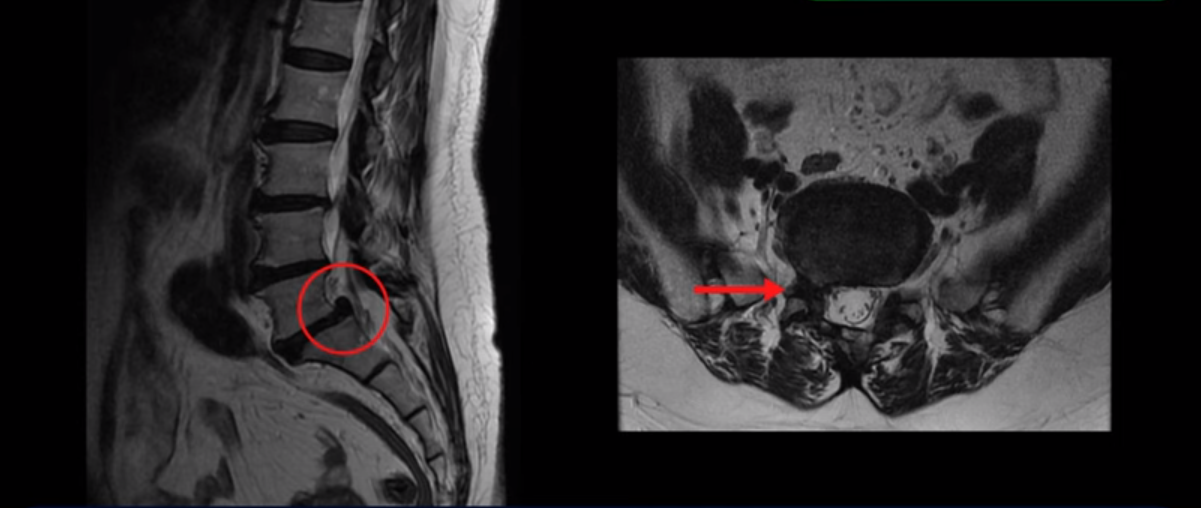

MRI를 보면 5번과 1번에 전방전위증과 척추분리증, 그리고 오른쪽으로 신경이 나가는 추간공을 막고 있는 디스크 탈출과 추간공협착증이 있습니다. 보시다시피 디스크와 뼈로 인해 신경이 나가는 구멍이 막혀 있습니다.